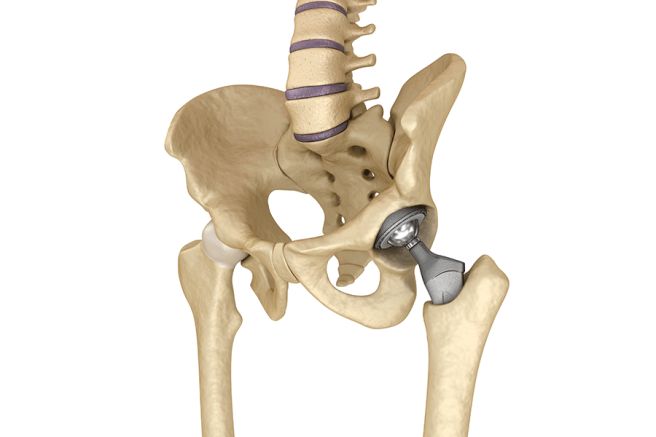

고관절 전치환술

대퇴골두 골절이나 심각한 골괴사가 동반된 고관절 골절에는 고관절 전치환술이 필요할 수 있습니다. 손상된 고관절을 인공 관절로 교체하는 방법으로 주로 고령자나 골절 후 회복이 어려운 경우에 시행됩니다. 수술 후 초기에는 입원 치료와 회복을 위한 물리치료가 필요할 수 있습니다.